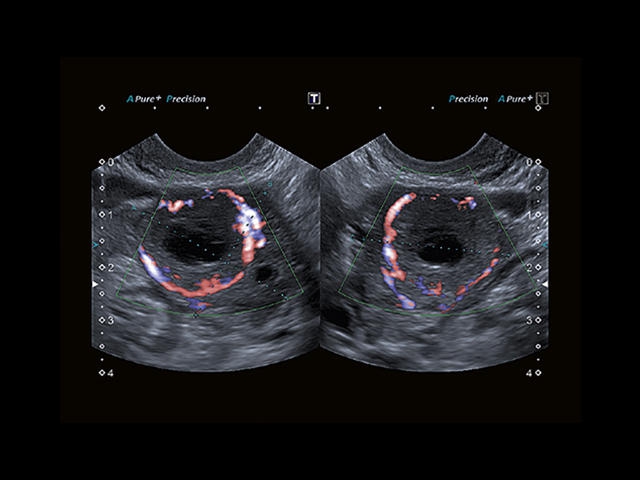

Обновленная версия легендарного УЗ-сканера. Стационарный аппарат экспертного класса Aplio 500 Toshiba NEW, визуализирует анатомические структуры в высоком разрешении. Модель позволяет выявить микрокальцификаты, новообразования, нарушения в работе сердца, сосудов и мышц. Присутствует функция виртуальной эндоскопии, 4D-сканирования, эластометрии тканей, УЗИ с контрастированием. За повышение качества изображения отвечают технологии ApliPure и Superb Microvascular Imaging. Первая задействует возможности пространственного и частотного кодирования, формирует цельный визуальный ряд с сохранением клинических маркеров. Вторая улучшает отображение микрососудистого русла, используя доплеровский эффект. Модель оснащена 21-дюймовым монитором, имеет 4 активных порта. Возможно подключение педиатрических, интраоперационных, лапароскопических и чреспищеводных датчиков.

Энергетический допплер:

Цветовой допплер: